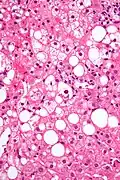

Mallory bodies are highly eosinophilic and thus appear pink on H&E stain. The bodies themselves are made up of intermediate cytokeratin 8/18 filament proteins that have been ubiquitinated, or bound by other proteins such as heat shock proteins, or p62/Sequestosome 1.[5]

Micrograph showing a Mallory body. Original magnification 200X. H&E stain. -